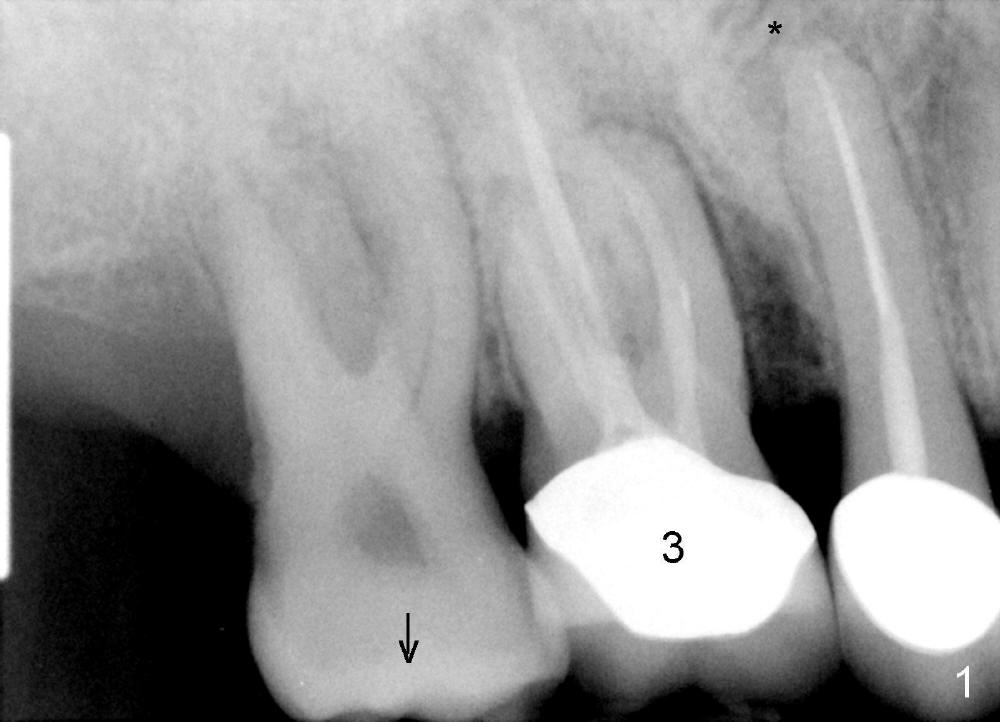

A 51-year-old man requests taking care of hemorrhage and odor associated with the tooth #3 (Fig.1). Due to religious and financial issues, the neighboring teeth will be treated later (supraeruption of #2 (arrow) and periapical radiolucency of #4 (*)). CBCT reveals that the septum of #3 is large enough to hold 4.5 mm implant (Fig.2). In fact osteotomy is created as planned in the septum using drills and taps (Fig.3 after removing 4.5x20 mm tap). Primary stability is obtained with a 4.5x20 mm implant (> 60 Ncm, Fig.4). The gap (*) is bone grafted; an abutment is placed (Fig.5 A); an immediate provisional is fabricated and cemented to cover the socket (Fig.6 P). When the socket heals in 3 weeks postop, the provisional and the abutment are removed for easy oral hygiene. Bone regenerates around the implant 3.5 months postop (Fig.7 *), but the 2nd molar has shifted mesially (arrow), presenting a restoration challenge.

Solution? An abutment is placed and a provisional crown with occlusal contact with the opposing is fabricated. A separator is placed between #2 and 3. Once a space forms, acrylic will be added the distal surface of the #3 temporary crown, which is then recemented. A new separator is used to create more space between these two teeth until #2 is distalized.

It appears that the upper molar shifting is quite common (6 7), probably due to less dense bone in the maxilla. It is the best to fabricate and keep an immediate provisional to hold the mesiodistal dimension and ask the patient to improve local oral hygiene during osteointegration. The implant crown is functioning 4 years 2 months post cementation while there is severe bone loss at #2 (Fig.8). An immediate implant could be placed at #2 (Fig.9), while a wide delayed implant will be placed at #31 (Fig.10).